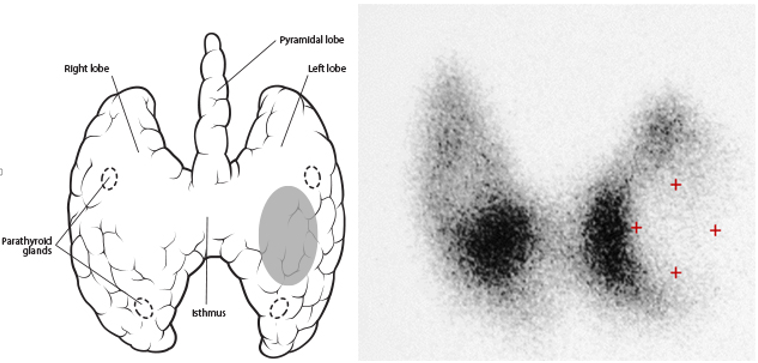

甲状腺冷结节是指用放射性元素作甲状腺扫描时,结节所在位置的放射性比附近正常甲状腺组织明显降低或接近无放射性,多见于甲状腺癌,但甲状腺囊肿、腺瘤、出

问题分析:甲状腺冷结节:医院核医学科,用ECT做甲状腺平面显像,在结论中出现的专业术语。冷结节表示该结节区域对放射性显像剂的浓聚程度比该区域周围的低,引

病情分析:根据结节对放射性核素的摄取能力分为"热结节"和"冷结节"。"热结节"是功能自主性甲状腺结节,几乎多为良性。"冷结节"则有癌的可能,但多个"冷

99mTcO4显像示左叶甲状腺中部外侧‘冷结节'99mTc-MIBI显像示左叶甲状腺中部‘冷结节'未见与亲肿瘤显像剂明显 首页内科内分泌科甲状腺瘤甲状腺冷结节的结论到底是啥